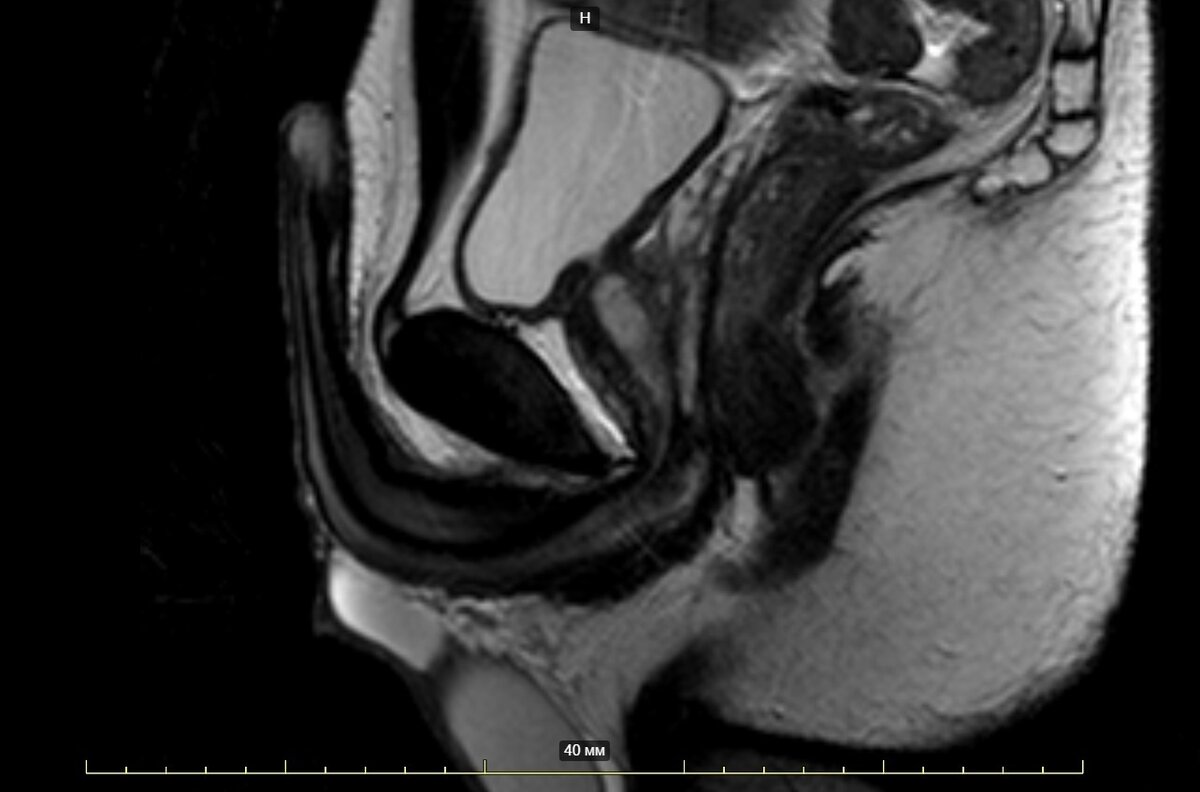

МРТ полового члена

МРТ полового члена в медицинских центрах СПб осуществляется как отдельное, независимое от МРТ органов малого таза у мужчин, исследование. Его цель - прицельно изучить мошонку, яички, половой орган, паховые каналы и сосудистую сеть области таза. Сделать томографию наружных половых органов можно на аппаратах мощностью от 1,5 Тесла по протоколу нативно или с контрастированием. От выбора модели аппарата МРТ и необходимости применения контраста будет зависеть финальная цена МРТ полового члена. Подсказать адреса диагностических центров в Санкт-Петербурге с нужным оборудованием и стоимость сканирования мочеполовой системы мужчины помогут специалисты Единого центра записи на МРТ и КТ. Мы также будем рады забронировать время для томографии в удобном для вас районе города. Звоните, если качественная диагностика по низким ценам - это ваш выбор!

Что покажет томография полового органа

В ходе МРТ полового члена врач-рентгенолог проверяет, что у пациента:

• Мошонка и ее содержимое правильно развиты и имеют обычную форму;

• Яички симметричные, нормальных размеров с однородной внутренней структурой. Каждое яичко имеет четкие и ровные контуры, фиброзная оболочка не утолщена;

• Придатки яичек имеют нормальные размеры, положение и внутреннюю структуру с двух сторон;

• Оболочки без патологических изменений с обеих сторон и без признаков скопления жидкости;

• Паховые каналы обычной формы и размеров;

• Пещеристые и губчатое тела не изменены;

• Ткани полового члена  носят цельный невоспаленный характер;

• Сосуды таза не изменены и бифуркация аорты происходит на должном уровне.

• Подвздошные артерии хорошо визуализируются и не содержат признаков стеноза.

• Бедренные артерии нормального калибра, с ровными стенками и гомогенным МР-сигналом просвета сосуда.

Все результаты томографии диагност отмечает в своем письменном заключении, которое обследуемый получает вместе с МРТ снимками по окончании диагностики. Если в ходе сканирования были выявлены патологические признаки, врач даст рекомендации по последующим шагам.